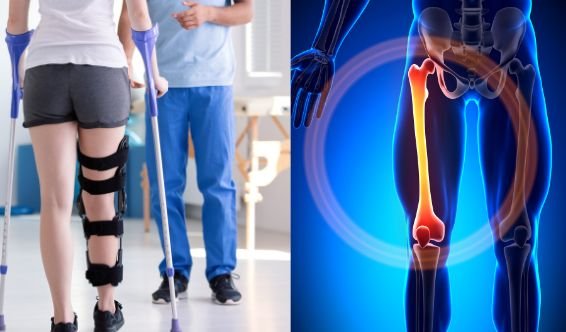

Fracture tibia / genou

Récupérer l'extension/flexion, renforcer quadriceps/fessiers, corriger la boiterie et reprendre les escaliers en sécurité.

Fracture fémur / hanche / bassin

Souvent après chute : reprise de marche progressive, endurance, transferts, et prévention du déconditionnement.

Séance de rééducation après fracture du col du fémur à domicile au Maroc

Fracture du col du fémur : reprise de marche progressive, transferts et autonomie.